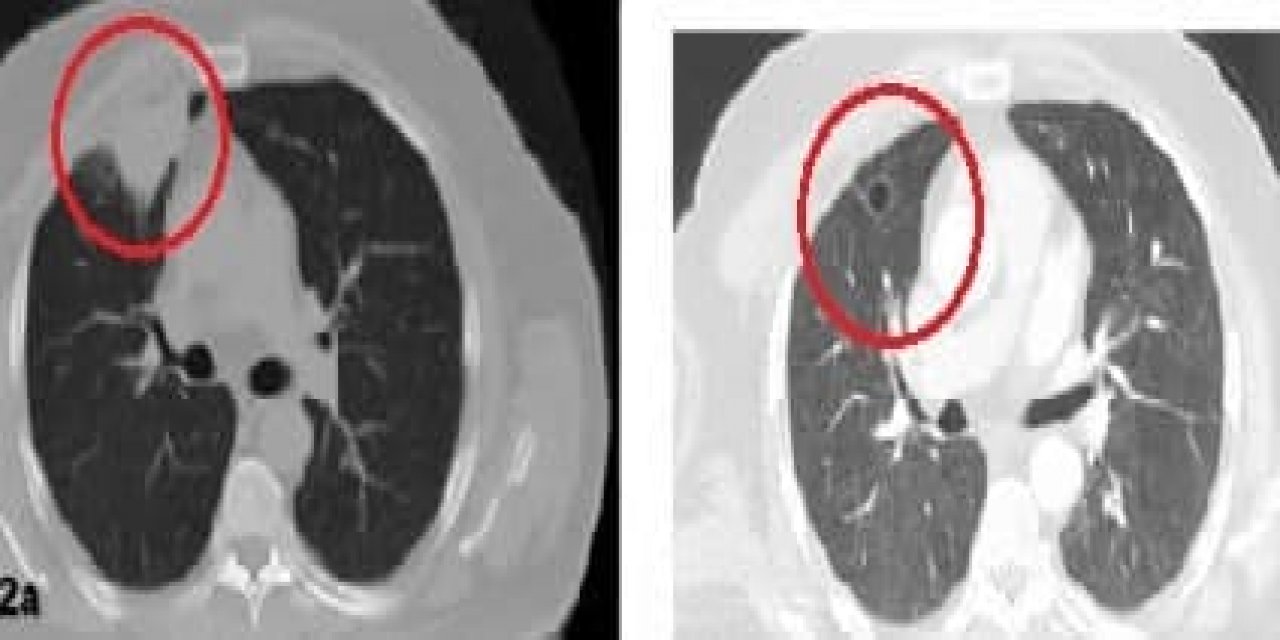

Korona virüs akciğer kanserini taklit etti